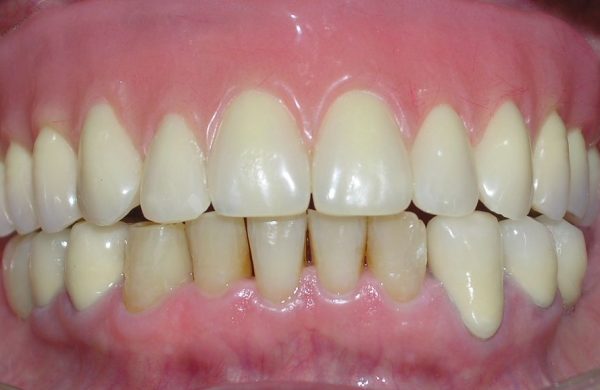

Foto final con la rehabilitación

Foto final de la sonrisa